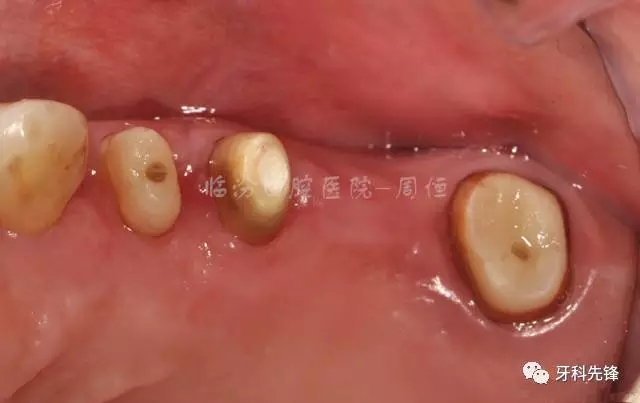

圖4 拆除原修復體牙列照

640.webp (5).jpg

圖5拆除原修復體側位咬合照

640.webp (6).jpg